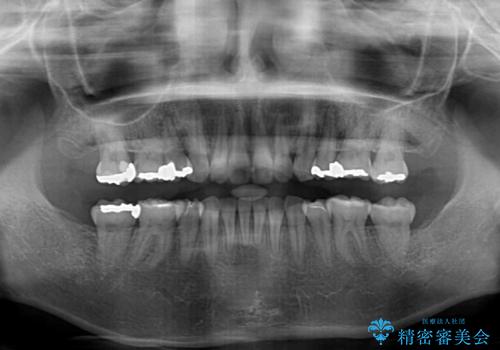

- 上下の出っ歯を気にして来院された患者様です。

口元を積極的に引っ込めるために、上下左右の第一小臼歯を4本抜歯することとしました。

元々ディープバイトのため、スペースを閉じている期間に上下前歯が接触してしまい、治療期間が想定よりも伸びてしまいました。